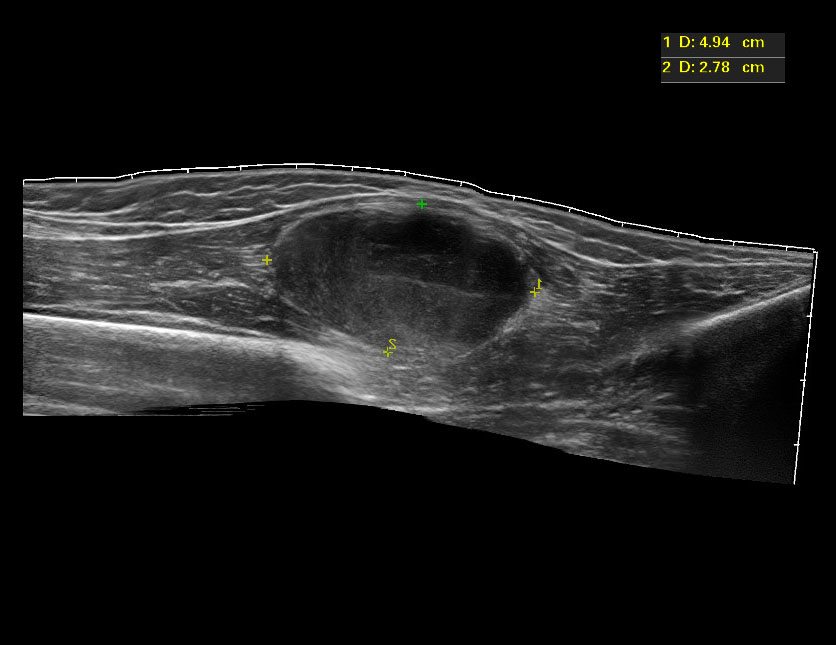

Девочка 12 лет, быстрорастущее образование на бедре.

C49 Злокачественное новообразование других типов соединительной и мягких тканей

C49.2 Соединительной и мягких тканей нижней конечности, включая тазобедренную область

Низкодифференцированная злокачественная опухоль периферического нерва.